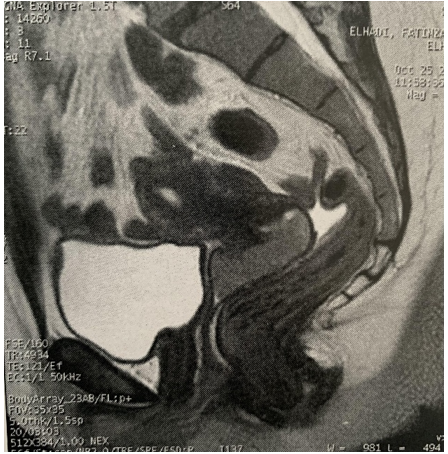

A pelvic MRI showed a cervical mass with discrete T2 hypersignal, diffusion hypersignal, T1 hyposignal, moderate and heterogeneous enhancement after injection of godalinium, measuring 57 x 40 mm and 55 mm in height, prolapsed into the vagina and responsible for infiltration of the proximal parametrium and the upper 1/3 of the vagina without pelvic lymphadenopathies; the ovaries were normal (figure 2).

Figure 2. Prolapsed cervical mass in the vagina, responsible for infiltration of proximal parameters and the upper third of the vagina